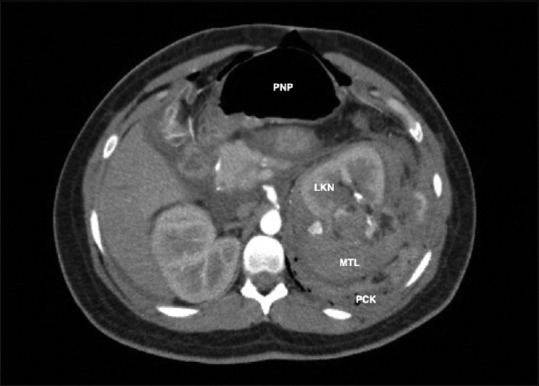

Wunderlich syndrome is characterized by the presence of abdominal pain, hematuria, and hypovolemic shock. We report a rare case of a 25-year-old pregnant woman, who came to the emergency department due to the sudden onset of low back pain and diaphoresis. The patient, during medical evaluation, experienced an altered state of consciousness. Diagnosed with hypovolemic shock, she was admitted to the operating room, where examination of the abdominal cavity revealed a left retroperitoneal hematoma. Damage control surgery was performed, but given the postoperative clinical deterioration, computerized tomography angiography of the abdomen was performed, showing a mass-like lesion arising from the upper pole of the left kidney, consistent with Wunderlich syndrome. Left nephrectomy was the definitive treatment for the 10-cm renal angiomyolipoma. Since Wunderlich syndrome is a potentially lethal entity, CT is usually the preferred diagnostic approach, and supra-selective vascular embolization is the first-line treatment.